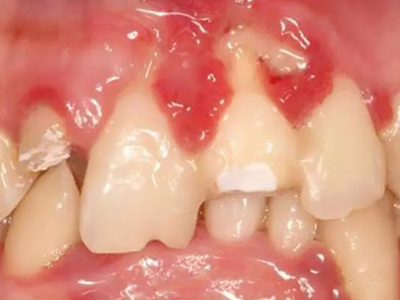

牙龈退缩多处牙龈萎缩出血图

牙龈退缩严重时,上排牙有多颗牙齿的牙龈部位发生退缩,导致牙根暴露,同时牙龈处还有出血的症状,伴有疼痛感,建议及时前往医院通过手术等手段进行治疗。